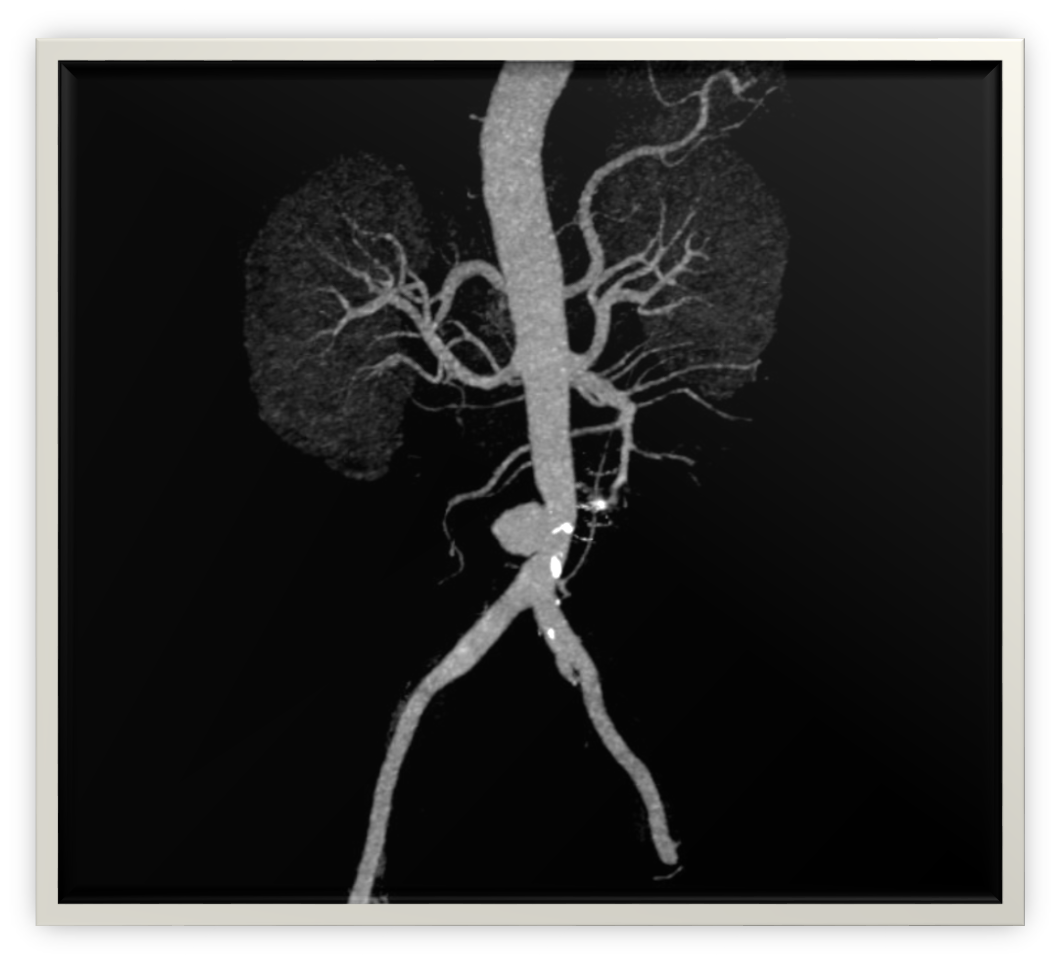

The patient maintained uncontrolled blood pressure after receiving 8 units of packed red blood cells and 4 units of fresh frozen plasma. CT mesenteric angiography demonstrated an infrarenal aortic saccular aneurysm at the level of L3-L4 measuring 36.6 x 39.4 mm anteroposterior (AP) and transverse (TR) [Figure 1], which partly contained thrombus and had an enlarged duodenal lumen space due to a suspected aortoenteric fistula near the proximity to the duodenal wall [4].

Figure 1. CTA Abdomen/Pelvis.